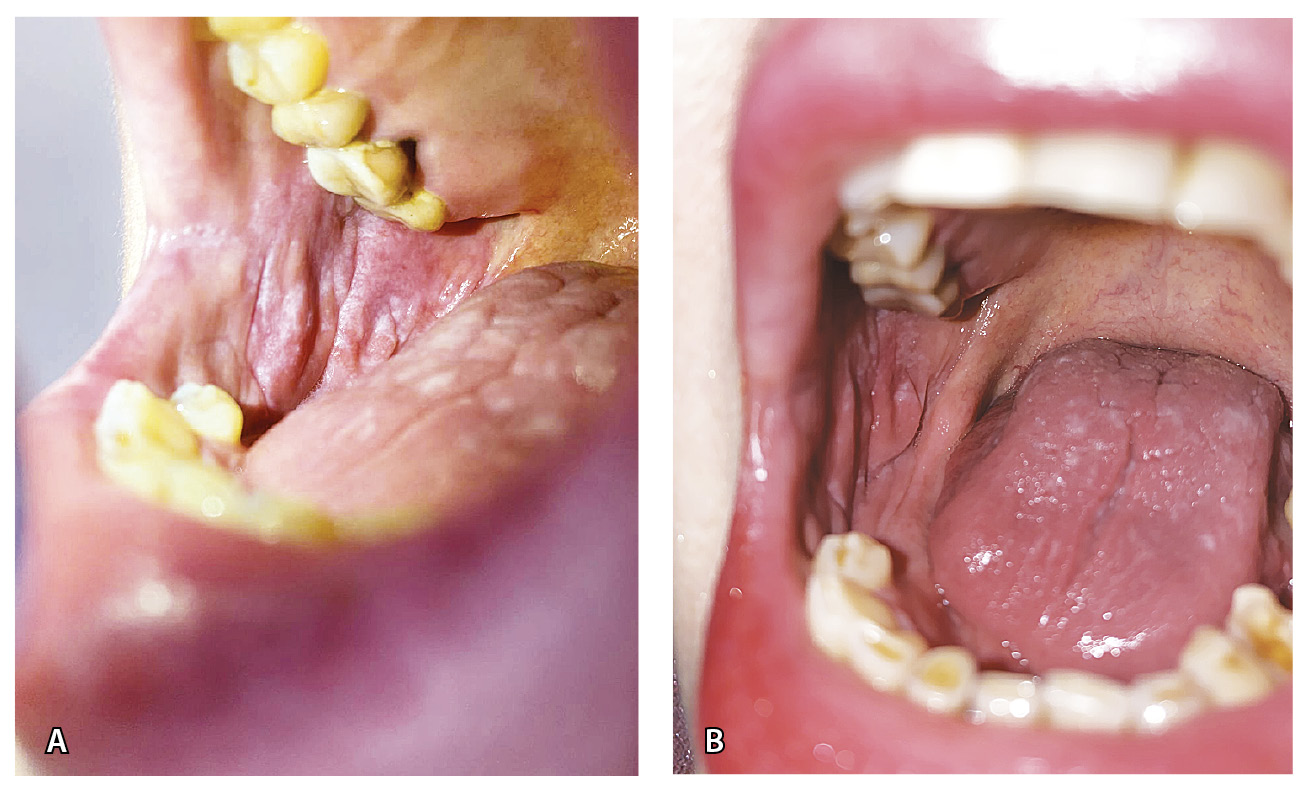

Кожа лица слегка отечна и гиперемирована, лицо имело «лунообразную» форму. На коже туловища в области груди и боковых поверхностей живота отмечались папулы розового цвета, единичные бляшки размером 1,0 × 1,0 см розового цвета с наслоением белых чешуек на поверхности (рис. 1). Феномен псориатической триады отрицательный. На коже волосистой части головы в затылочной области – очаг размером 3,0 × 2,0 см, в центре которого наслоение плотных серебристых чешуек, по периферии – область гиперемии (рис. 2А). На ладонной и боковой поверхности первого и второго пальцев правой кисти – участки гиперкератоза желтого цвета с белыми чешуйками (рис. 3). На коже паховой области, больших половых губ – папулы синюшного цвета, полигональные вытянутые с блеском при боковом освещении. На слизистой больших и малых половых губ, ануса – белесоватые папулы, сливающиеся в бляшки (рис. 4А). На слизистой щек – белесоватые папулы, сливающиеся в ретикулярные бляшки, отдельные белесоватые папулы – на спинке языка (рис. 5). На красной кайме нижней губы в латеральных частях – белесоватые вытянутые бляшки размером 1,0 × 0,5 см. Субъективно пациентка отмечала зуд в области гениталий.

Рис. 5. Лихеноидные высыпания на слизистой оболочке полости рта и языка (правая щека): А – до лечения, Б – после лечения

Через 6 недель после начала наружной терапии отмечена положительная динамика: разрешение высыпаний на слизистой гениталий, пигментные пятна на месте папул на коже паховой области и больших половых губ (рис. 4Б), уменьшение количества высыпаний на слизистой полости рта и языка (рис. 6), разрешение бляшек на красной кайме нижней губы, разрешение центральной части очага в затылочной области (рис. 2Б). Единичные папулы и бляшки на коже туловища и очаги на пальцах кисти сохранялись.

Рис. 6. Лихеноидные высыпания на слизистой оболочке полости рта и языка (левая щека): А – до лечения, Б – после лечения

В нашем наблюдении отмечалось сочетанное поражение слизистой оболочки полости рта и языка, слизистой вульвы, проявляющееся в виде белесоватых удлиненных папул, которые местами сливались в ретикулярные бляшки. На коже больших половых губ и паховой области наблюдались отдельные папулы синюшного цвета, полигональной формы. Таким образом, имелось сочетанное поражение слизистых оболочек и кожи. Для проведения дифференциального диагноза с красным плоским лишаем было проведено гистологическое исследование, при котором выявлялись очаги паракератоза и незначительного гранулеза, инфильтраты в верхней дерме с примесью эозинофилов, что указывало на лихеноидную токсическую реакцию. В литературе встречаются описания как лихеноидной токсической реакции, имитирующей красный плоский лишай, так и красного плоского лишая, индуцированного приемом иматиниба. Описаны единичные случаи не только одновременного поражения кожи и слизистых оболочек, но и вовлечения ногтевых пластинок. Так, подобная триада встречалась у 31-летнего мужчины, страдающего хроническим миелоидным лейкозом с филадельфийской хромосомой (Ph+), получавшего иматиниб 400 мг/сут в течение 5 месяцев [20]. У него наблюдались генерализованные зудящие фиолетовые папулы, узелки и бляшки, симметрично поражающие кожу груди, рук, ладоней, бедер и подошв, а также поражение красной каймы губ, слизистой оболочки щек, языка и гениталий. Кроме того, на одной ногтевой пластинке образовались продольные бороздки. Совокупность подобных изменений (кожа, слизистые оболочки, ногтевые пластинки) позволяла заподозрить развитие у пациента красного плоского лишая. Но гистологическое исследование очага с кожи, при котором визуализировался очаговый паракератоз, экзоцитоз лимфоцитов в верхний эпидермис, глубокий периваскулярный инфильтрат с наличием эозинофилов, выявило лекарственную лихеноидную реакцию, что подтверждает необходимость морфологической верификации диагноза в подобных случаях.

Для лечения псориазиформных очагов мы рекомендовали использовать метилпреднизолона ацепонат, что через 6 недель привело к регрессу части высыпаний, в частности, центральной зоны очага на волосистой части головы в затылочной области, однако некоторые бляшки на коже туловища и участки гиперкератоза на пальцах кисти сохранялись. Значительный эффект был получен в результате применения на лихеноидные высыпания на коже и слизистых оболочках 0,1% мази такролимуса. Регресс высыпаний на слизистой гениталий, папул в паховой области, бляшек на красной кайме нижней губы констатировали через 6 недель ежедневного использования, на слизистой полости рта и языка количество высыпаний существенно уменьшилось. Прием иматиниба в дозе 400 мг/сут пациентка не прекращала. Мазь такролимуса является терапией первой линии при поражении слизистых оболочек красным плоским лишаем и успешно применяется при данном заболевании. Мы впервые эффективно использовали ее для лечения лихеноидных лекарственно-индуцированных высыпаний на слизистых оболочках на фоне приема иматиниба, хотя в доступной нам литературе подобного опыта не встретили.